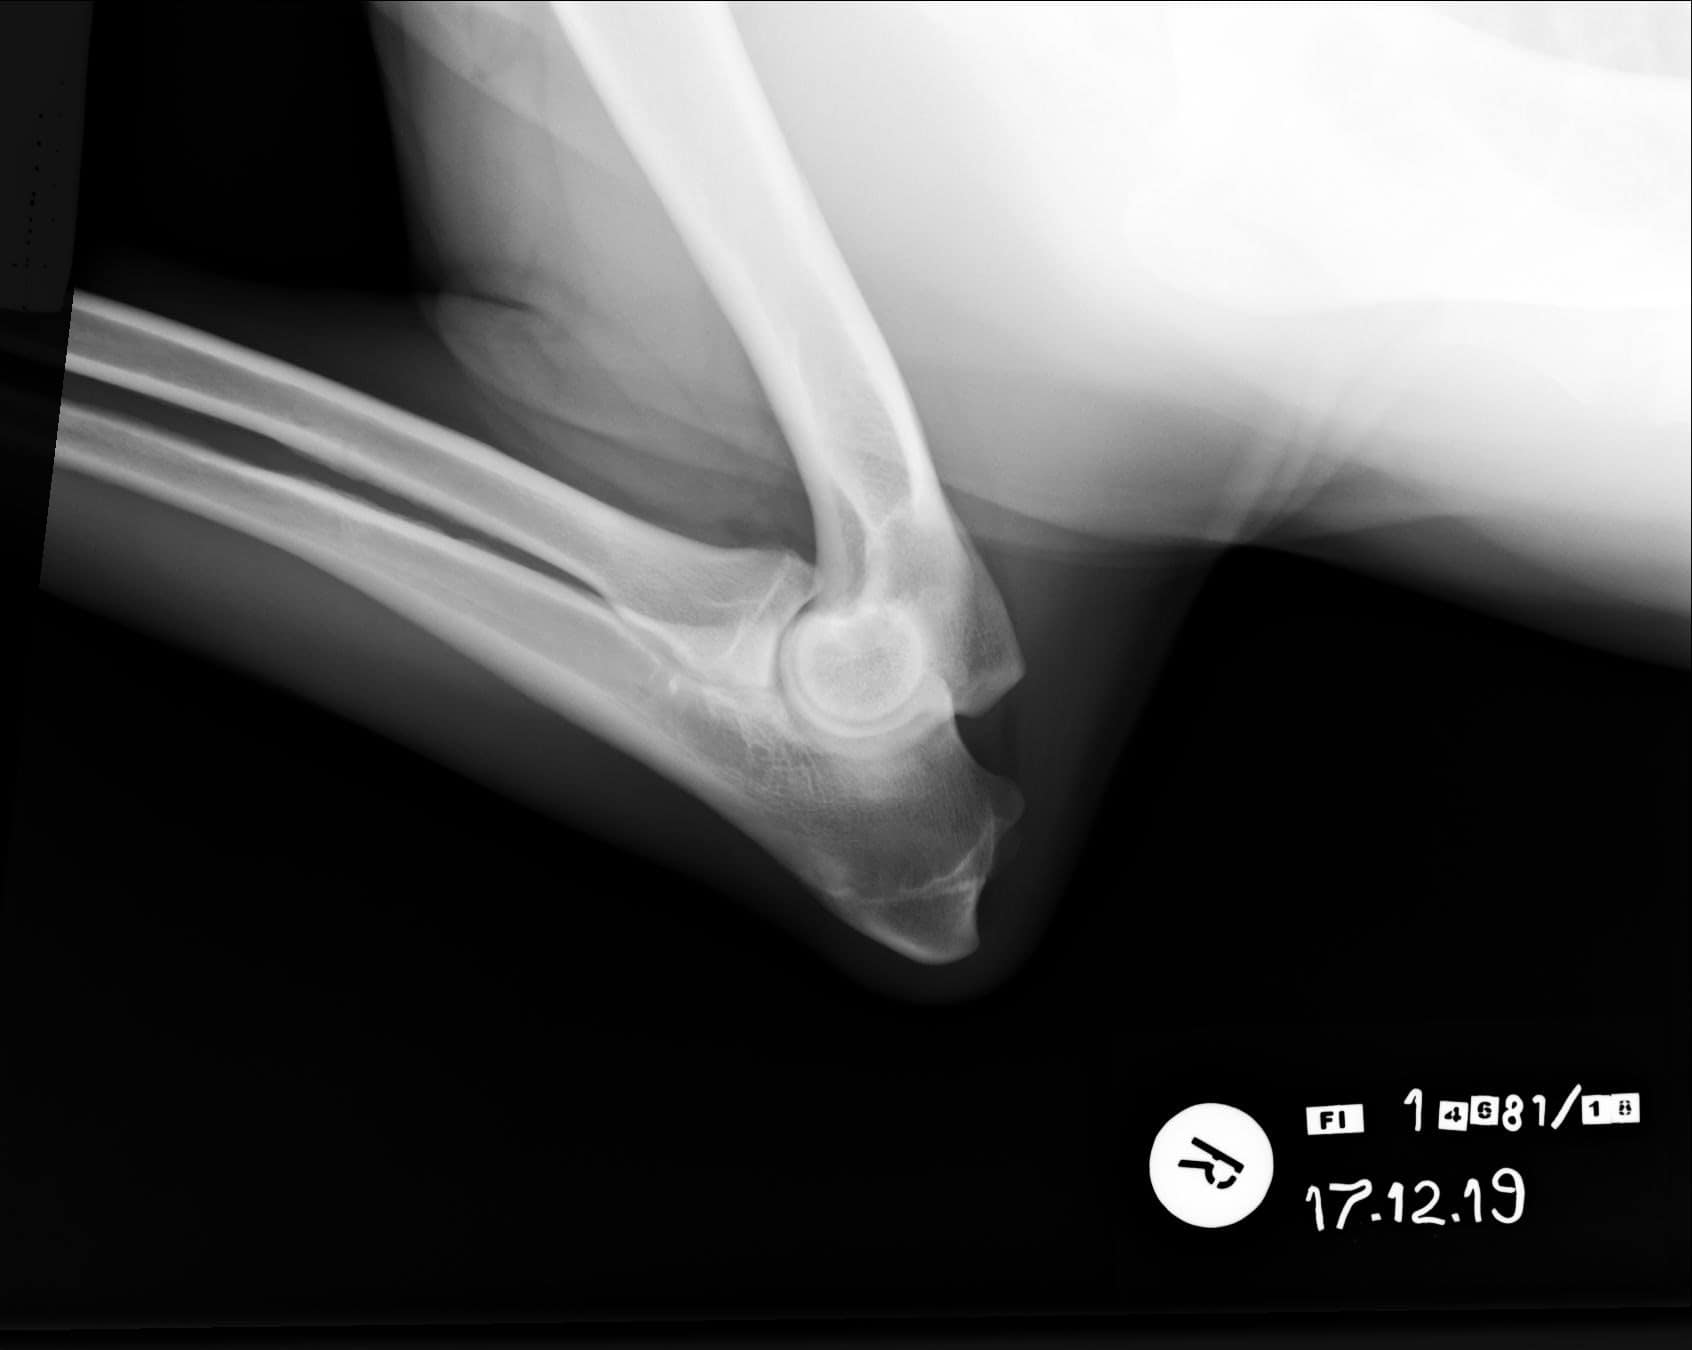

Tähän mennessä Iivo on ollut täysin terve ja Iivo tutkittiin luustoltaan terveeksi joulukuussa 2019. Luonnekuvaukseen (MH, laukausvarma) Iivo osallistui elokuussa 2020.

| Kyynärät: | 0/0 |